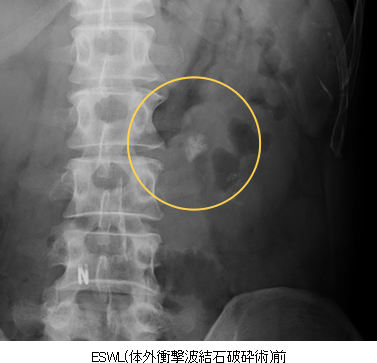

- 結石破砕

- X線とエコーを使って結石に焦点をあわせ、衝撃波で結石を割っていきます。